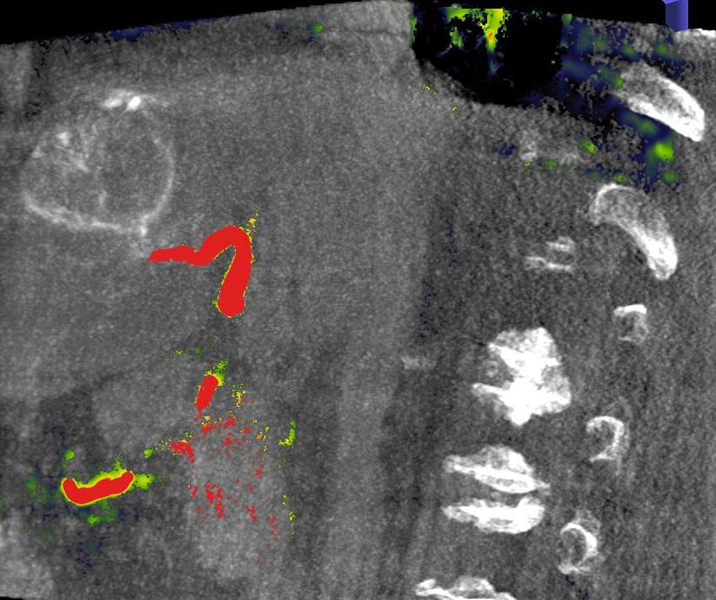

Abbildung: Bei diesem Patienten wurde ein im Röntgen nur schlecht sichtbarer Knochentumor vor der Operation unter MRT-Kontrolle mit kleinen röntgendichten Spiralen („Coils“) markiert. Damit hat der Operateur eine optimale Darstellung des Tumorbereichs bzw. der Tumorgrenzen und kann gezielter, schonender und effektiver operieren.